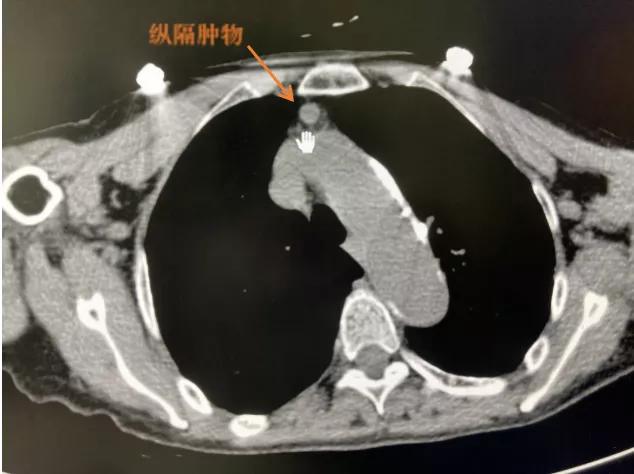

78岁的杭州人钱奶奶,五年前在当地医院体检做胸部CT时,发现前纵隔肿物,当地医院医生告诉钱奶奶,“考虑肿瘤可能,需要手术治疗”。由于钱奶奶 以前得过肺结核和结核性胸膜炎,有不少后遗症,手术风险较大 。而且钱奶奶自己没什么不舒服,对手术又比较恐惧,所以一直没敢手术,就这样一直拖着。

近期,钱奶奶到杭州市红十字会医院体检复查CT,发现五年前的前纵隔肿瘤 直径已经增大到1.5cm 。

“纵隔是胸部的‘隐匿角落’,对许多人来说都有些陌生。纵隔肿瘤慢慢长大,会 对周围的心脏、大血管、气管、食管等重要脏器产生压迫 ,导致严重的不良后果。”听完医生的分析,在家属的劝说下,钱奶奶同意住院治疗。